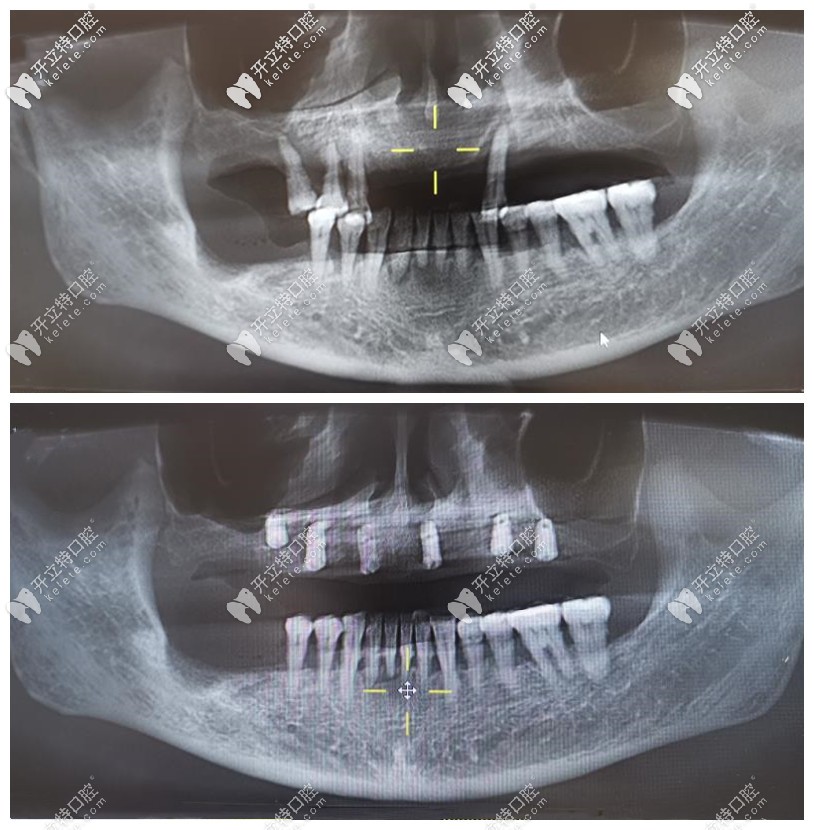

牙管家姜琳博士科普:牙周炎顧客是否可以做牙齒矯正

姜琳博士表示,牙周炎顧客能不能做矯正,主要還要看拍片等情況。一般情況下,如果牙周炎顧客做矯正的話,首先需要的是先治療牙周炎,等情況允許之后再做。

不過這類顧客做牙齒矯正時,不僅要特別注腔衛(wèi)生,定期進行潔牙,矯正速度相對比一般人來說,也要慢的多。